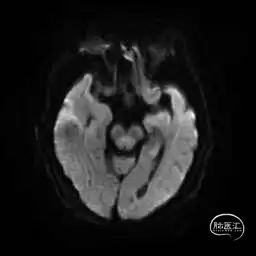

MRI提示小脑缺血性改变。

术后9天MRI: